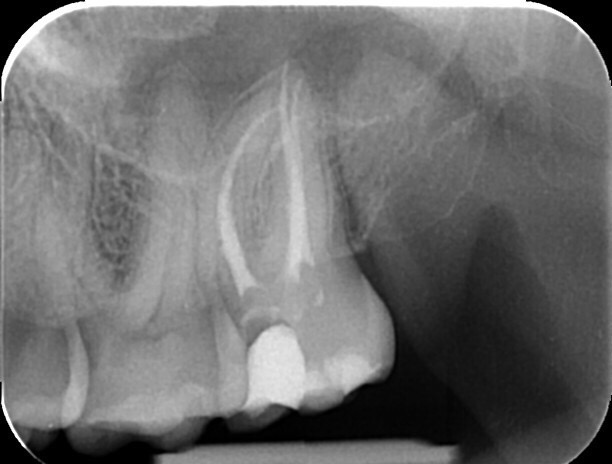

Zobe moramo zdraviti kadar pride do vnetja zobnega živca (pulpe) ali njegovega odmrtja (gangrena). Če kariesa ne odstranimo pravočasno, ta doseže zobni živec. To je lahko za vas popolnoma neboleče in brez težav, običajno pa se kaže s klasičnim zobobolom, ki se po moči lahko meri z najhujšimi telesnimi bolečinami. Zdravljenje zoba ponavadi zahteva več obiskov, ravno pri tem posegu pa je uporaba operativnega dentalnega mikroskopa najpomembnejša. Med zdravljenjem se poslužujemo tudi pomoči rentgenskih posnetkov, v zelo zahtevnih primerih pa tudi CBCT slikanja (cone-beam computed tomography – ali po slovensko – računalniška tomografija).

Granulom je kronično vnetje na koncu korenine zdravljenega ali gangrenoznega zoba. Vnetje povzročajo bakterije, ki so ostale v zobni korenini po zdravljenju. Skoraj 90% vseh granulomov ne povzroča bolečin. Zobozdravniki pa radi označujemo granulome z izrazom “tempirana bomba”. Granulom lahko namreč 10, 20 ali celo več let ne dela težav, počasi raste in topi kost, na enkrat pa izbruhne in vam začne delati ogromne težave. Glavne težave so bolečina, huda oteklina, vročina in splošno slabo počutje.Zato je nujno, da granulome opazimo pravočasno s pomočjo rentgenske diagnostike in jih skušamo s pomočjo endodontskega zdravljenja pozdraviti. Pogosto je ob izbruhu namreč edina rešitev odstranitev (puljenje) zoba.

Mnogo ljudi ima enega ali več zdravljenih zob. Zdravljenje zob je, zaradi komplicirane anatomije (zgradbe) zob, zelo zahtevno. Zato je žalostna resnica, da je večina zob, ki je bila zdravljena pred več kot 10 leti, zdravljena slabo. Take zobe je potrebno rentgensko kontrolirati, in v primeru, da opazimo na koncu korenin kronične spremembe, tudi ponovno zdraviti. Ponovno endodontsko zdravljenje lahko vključuje tudi poseg apikotomije. Če zdravljenje iz določenih razlogov ni možno, ni uspešno, ali pa je napoved izida zelo slaba, svetujemo odstranitev zoba in nadomeščanje z zobnim vsadkom ali mostičkom.